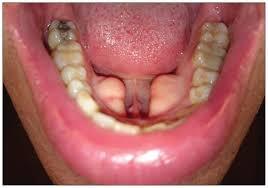

Mandibular tori

Appear on the lingual aspect of the mandible in the premolars. Usually bilateral, lobulated, or nodular. (Tori is the plural of torus)

Tori and Exostosis: radiographs

appear as a radiopaque mass

Tori and exostosis tx

Not needed unless the tori interfere with speech, prosthetic appliances, or swallowing.